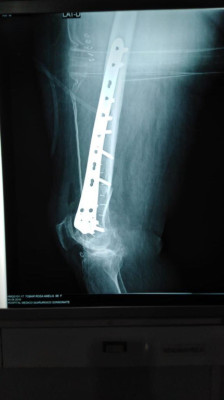

Imágenes de ortopedia y traumatología

Envíado por Dr. José Israel Flores Hernández